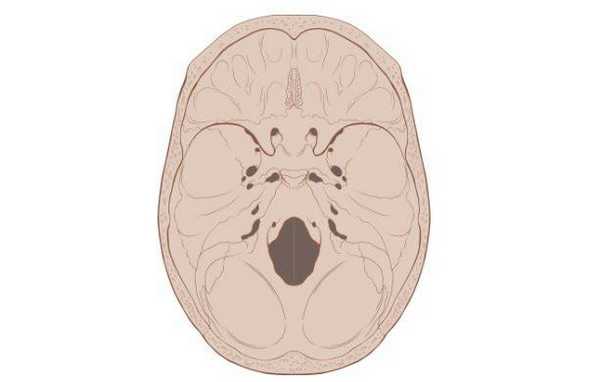

![Схематическое изображение основания черепа]()

Схематическое изображение основания черепа

Основание черепа - область, образуемая затылочной, височными, решетчатой, лобной и клиновидной костями. Внутренняя поверхность данной анатомической структуры играет роль площадки, на которой покоится головной мозг. Через большое отверстие затылочной кости проходит ствол мозга. Наружная поверхность основания черепа богата нервными волокнами, кровеносными сосудами, связками и сухожилиями.

![3D-реконструкция с помощью компьютерной томографии]()

Основание черепа: вид изнутри и снизу